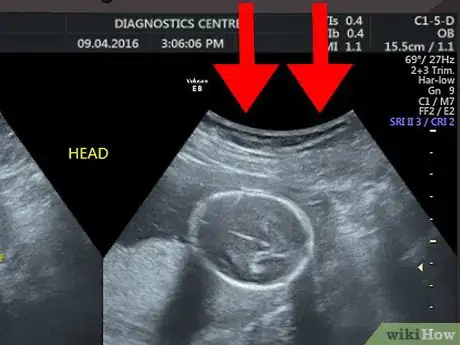

1Disregard the text and numbers at the top of your scan. Most hospitals and ultrasound centers use this space to include details like your name, hospital reference number, or ultrasound machine settings. Since this information does not have anything to do with what you see on the ultrasound image, you can ignore this information.[1]

2Start from the top of the image. The top of the screen or printed image is where the ultrasound probe was placed. In other words, the image you see shows what the organ or tissues look like from the side rather than from the top.[2]

- For example, if you are having an ultrasound of your uterus, then what you see at the top of the screen or printed ultrasound would be the outline of the tissues above your uterus. As you look further down the screen, you will see deeper tissues, such as the lining of your uterus, the inside of your uterus, and the back of your uterus.